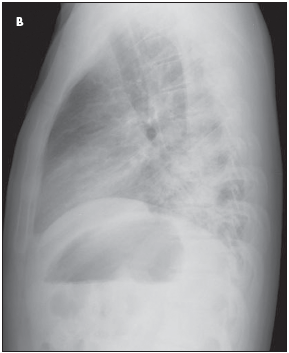

Coarse crackles were heard throughout the upper and lower lung fields bilaterally, and breath sounds were decreased. The abdomen was soft and nontender without hepatosplenomegaly. Compared with previous imaging studies, lateral (B) and posteroanterior (C) chest radiographs showed worsening pulmonary edema and bibasilar pulmonary opacities with air bronchograms. A CT scan confirmed the presence of severe bilateral pneumonia.